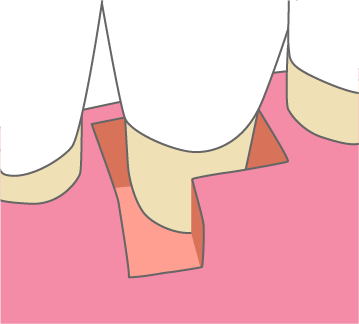

歯周組織再生療法は施術の難易度が高く、ほとんどの歯科では扱っていない内容です。

専門医資格を持つ医師が歯周組織再生治療を手がけるので、安心して治療を受けていただけます。